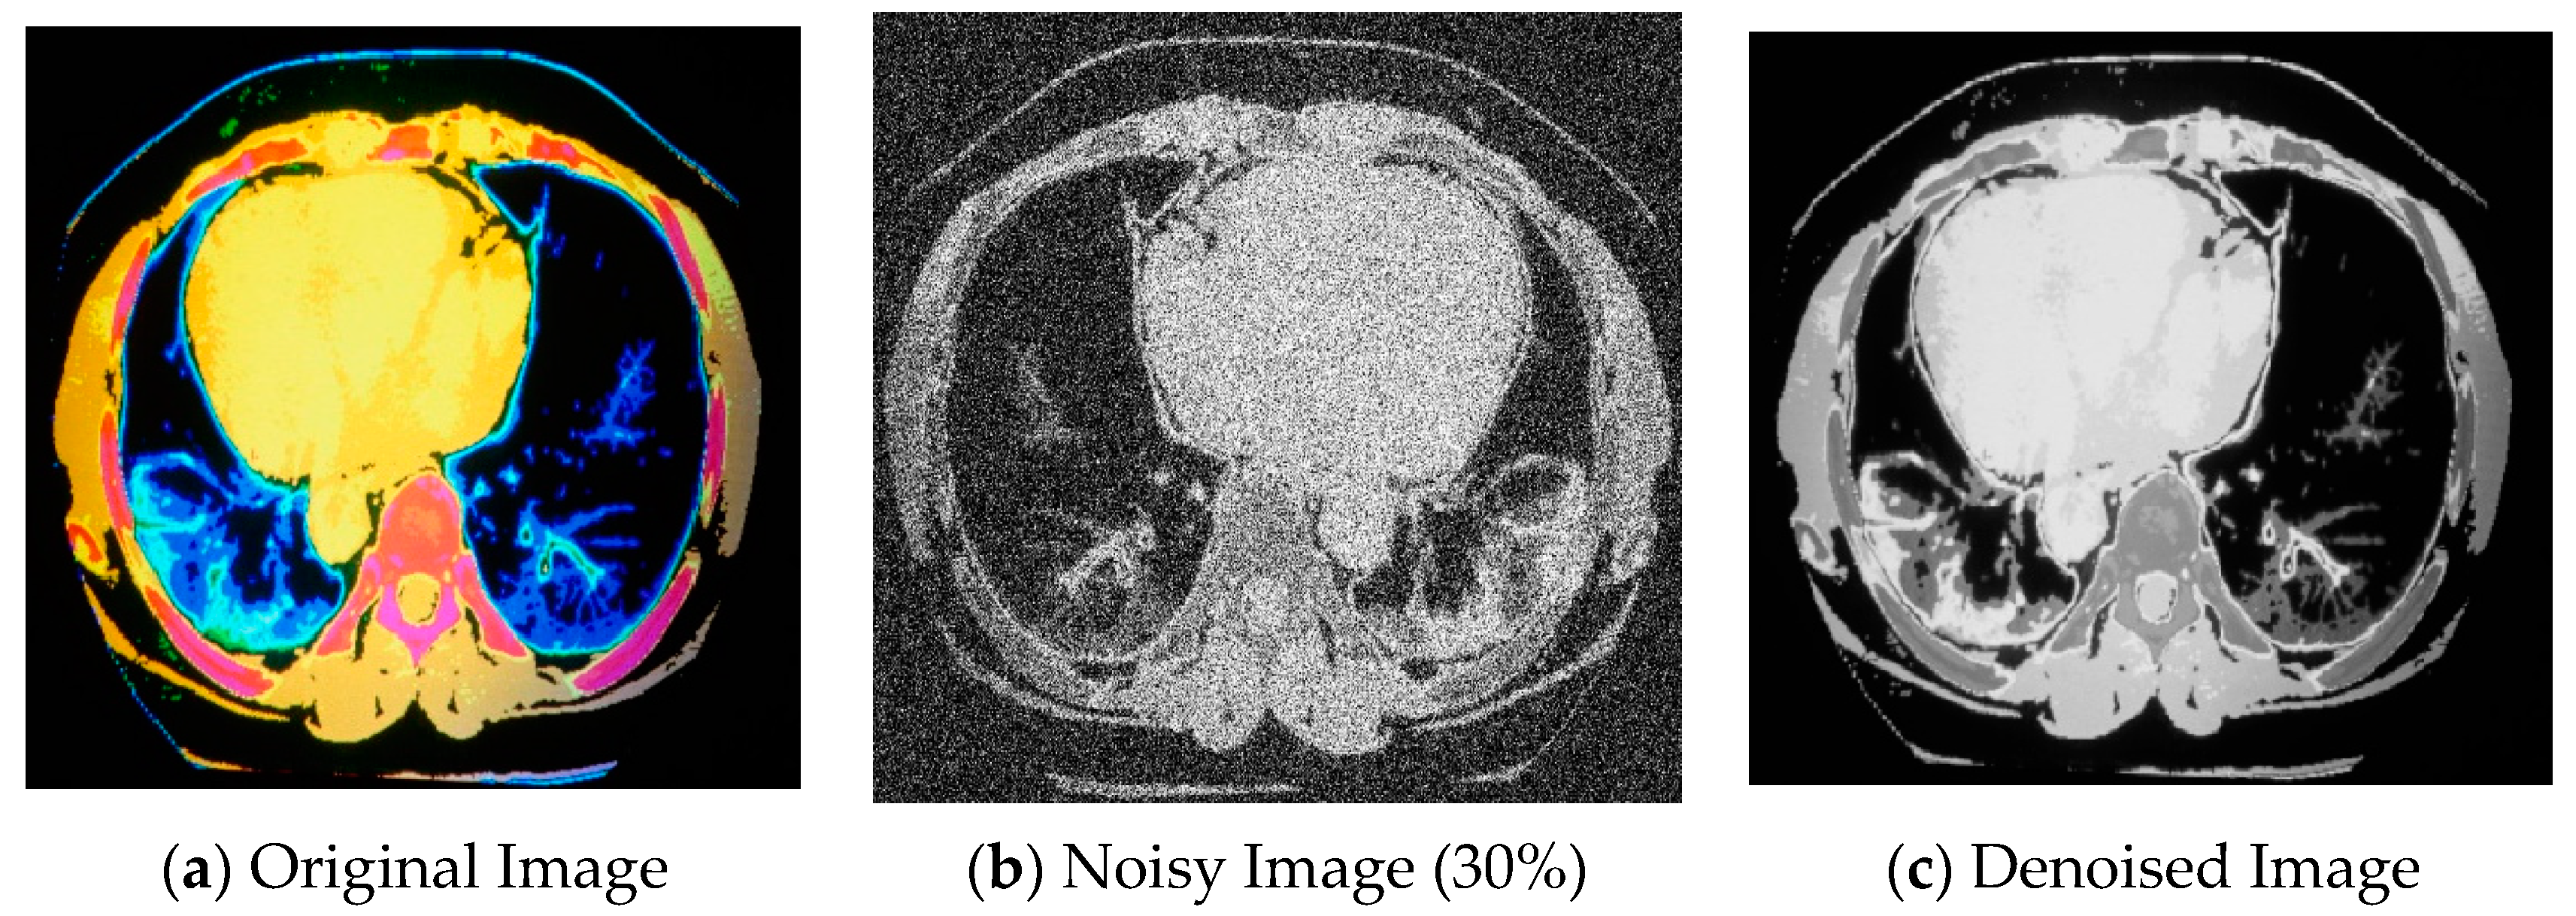

The qualitative analysis visually compared the denoised image with an original noisy image. Noise reduction and preservation of image details were observed, whereby the denoised image appeared smoother and cleaner than the noisy image, with reduced visual artifacts caused by noise. Additionally, the denoised image exhibited a similar structure and pattern as the original image, indicating effective denoising. The intensity profiles were analyzed to assess the preservation of fine details. Intensity profiles are one-dimensional plots of pixel intensity values along a specific line or region of interest in the image. By comparing the intensity profiles of the denoised image with the original image, it verified whether important features and edges were well preserved in the denoised result. The qualitative analysis for denoising CT images is demonstrated in Figure 2.

Figure 2.

(a) Original image [55], (b) noisy image (30%), and (c) denoised image.

In Figure 2, the original image in (a) was applied with a grayscale filter in combination with an AGBN with a 30% noise level. The image was degraded after adding Gaussian blur noise, as shown in (b). The denoised image in (c) was generated by applying an anisotropic Gaussian filter, which suppressed the Gaussian noise while preserving edges by using more smoothing in the regions with little variations and less smoothing in the areas with solid intensity gradients. Anisotropic Gaussian filters enhanced the sharpness and overall image structure. Haar transform was then applied to decompose the noisy CT scan images into different frequency bands, including approximation and detail coefficients. Mainly, it analyzed and detected abrupt changes in intensity, such as edges in an image. Removing noise and lower-frequency components while retaining high-frequency information related to the edge helps enhance edge details and reduce blurring. Finally, the DnCNN was trained on a noisy and corresponding clean images dataset to learn the noise patterns and underlying structures. It took a noisy image as input during inference and used its learned knowledge to estimate and remove the noise. By eliminating the noise from the image, the DnCNN effectively reduced blurring caused by noise-related artifacts.